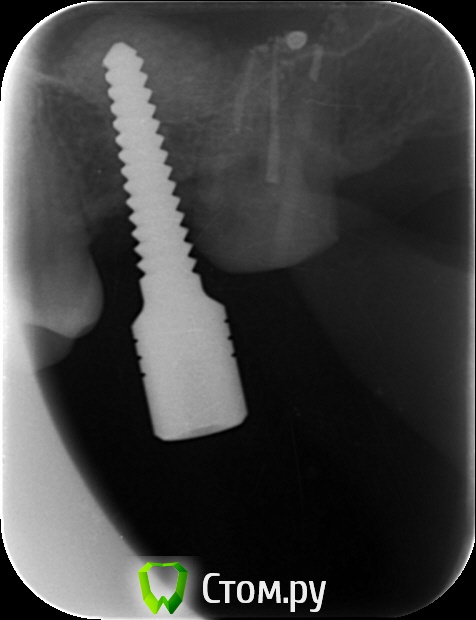

an_ver Опубликовано 29 мая, 2014 Поделиться Опубликовано 29 мая, 2014 Закрытый синус.Набор SCA.SPI 3,75*10 мм 5 Ссылка на комментарий

4ebstom Опубликовано 29 мая, 2014 Поделиться Опубликовано 29 мая, 2014 Имплант недокручен или снимок такой? Ссылка на комментарий

an_ver Опубликовано 29 мая, 2014 Автор Поделиться Опубликовано 29 мая, 2014 Имплант недокручен или снимок такой?Наверно снимок косой)) Счас с формиком ходит.Поставлю коронку отфотаюсь))) Ссылка на комментарий

an_ver Опубликовано 30 мая, 2014 Автор Поделиться Опубликовано 30 мая, 2014 1. Сколько в итоге подняли?2. Имплант какой длины?3. У Вас Rg в кабинете стоит?1. 4 мм 2.3,75*10 мм SPI 3.Rg да,в каждом своя пушка...дорого но удобно..RVG без проводов Дигора Ссылка на комментарий

an_ver Опубликовано 30 мая, 2014 Автор Поделиться Опубликовано 30 мая, 2014 Это от набора Мис...немного уплотнил,перед закручиваниемГрафт МР3 от Остебиола.В наборе есть типа нагнетателя как раньше под амальгаму Ссылка на комментарий